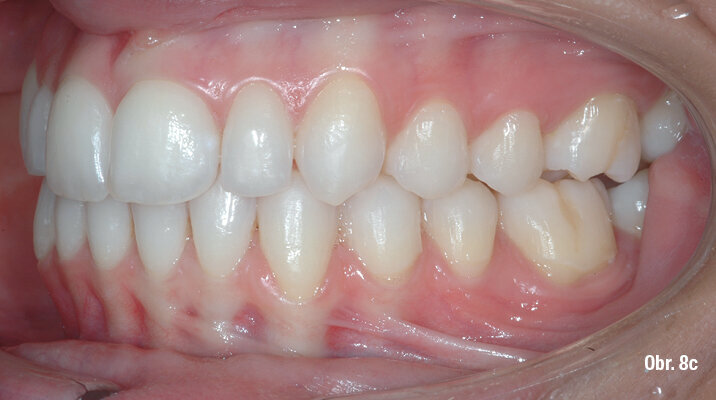

Klinický výsledek byl vynikající, postavení molárů i špičáků v I. třídě, vyhovující překus a předkus. I profil dolní třetiny obličeje byl výrazně lepší.

Na překrytí kefalometrických snímků je zřejmá distalizace molárů o 6 mm bez výraznějšího sklonu a s ideálním bukolingválním sklonem řezáků. Tahy druhé třídy umožnily protrakci mandibuly o 1,5 mm. Jako retenční aparáty jsme zvolili Vivera retainery (Align Technology) (obr. 6, 7a–c, 8a–c).